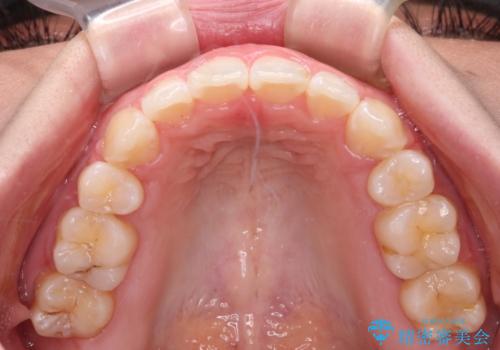

骨格的に下顎骨が前方位にあるため、口元の突出感改善には限界があると思われましたが、唇の閉じにくさが改善するほど引っ込めることができました。

- 口元の突出感と口の閉じにくさ、前歯のデコボコを気にして来院された患者様です。

上下左右第一小臼歯4本を抜歯し、ワイヤー装置にて口元を引っ込めるよう矯正治療を行うこととしました。